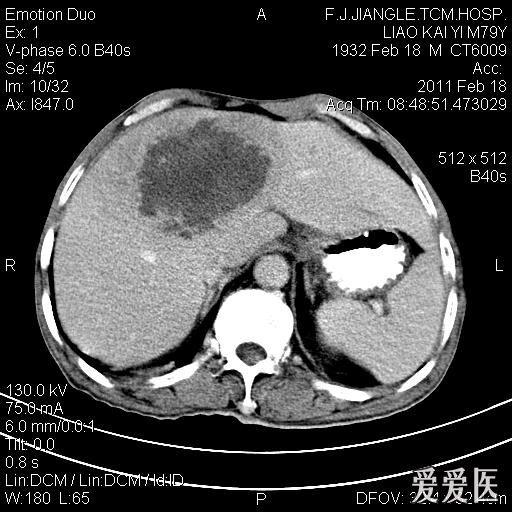

引起細(xì)菌性肝膿腫的病菌主要是大腸桿菌等。常見(jiàn)的肝膿腫有細(xì)菌性和阿米巴性兩種。細(xì)菌性肝膿腫的主要臨床表現(xiàn)是發(fā)熱,寒戰(zhàn)和腹痛。引發(fā)肝膿腫的病因有很多種,最為熟知的是阿米巴性肝膿腫和細(xì)菌性肝...